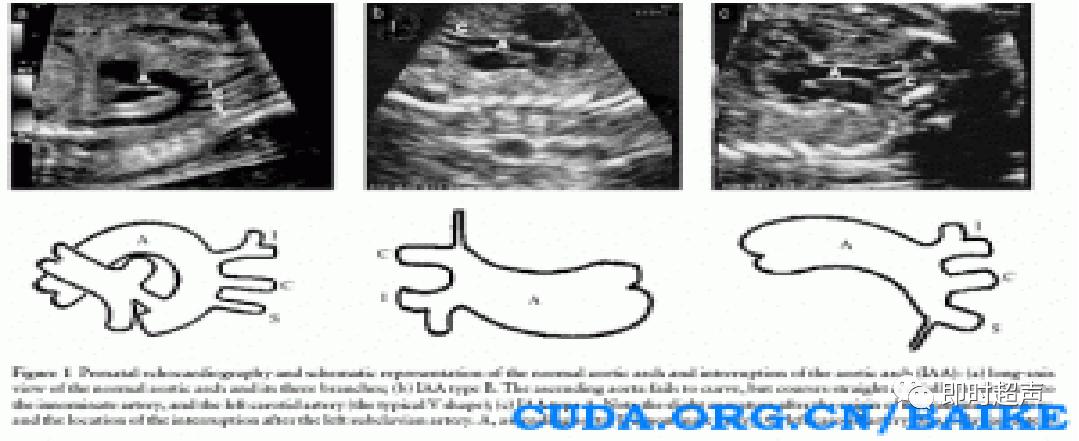

主动脉弓离断

主动脉弓离断定义:升主动脉与降主动脉之间的主动脉弓离断,下肢血供通过动脉导管由右心提供。分类主要根据中断位置与头臂血管的相对关系。A型:左锁骨下动脉远端中断。B型:左颈总动脉远端中断。C型:头臂干远端中断。

解决方案:

显示三血管气管切面时侧动探头,显示主动脉弓肺动脉汇入降主动脉